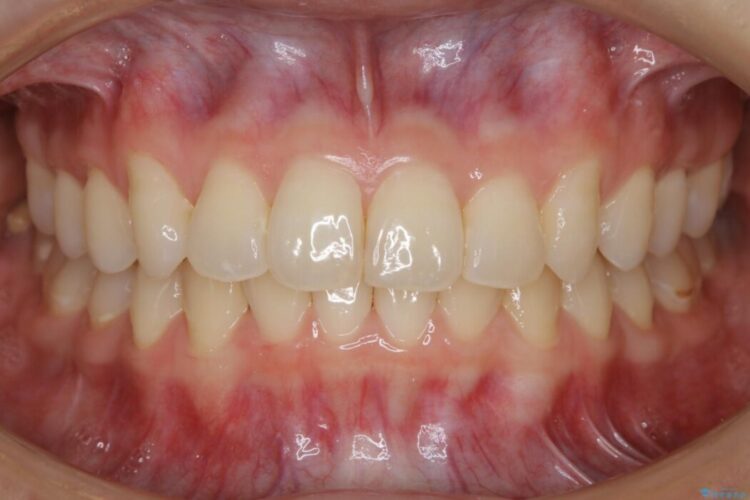

【20代女性】ブライダルに向けた矯正できれいなスマイルラインへ

- 患者様:20代女性

- 治療期間:1年10ヶ月

- 矯正装置:インビザライン コンプリヘンシブパッケージ

笑った時に見える歯並びをきれいにしたいとの主訴で来院されました。

ガタつきの度合いから抜歯は不要と判断しましたので、マイクロインプラントを用いて歯全体を遠心移動させていくことでねじれや噛み合わせのズレを改善していく計画を立てました。